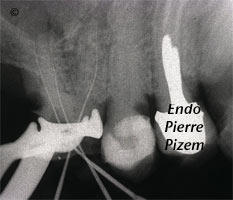

L’apport de l’OPMI PROergo lors du retrait d’un fragment de Lentulo dans le tiers apical du canal mésio vestibulaire

Étude de cas numero: 491047 Image 1: Fragment de